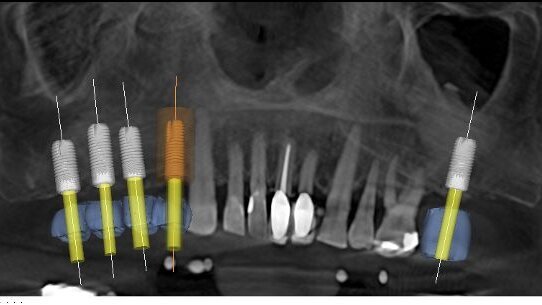

Les cas suivants démontrent les types des plans de traitement implantaires, qui peuvent être traités en utilisant des techniques chirurgicales guidées par la TDM (tomodensitométrie) 3D et par l'intégration de GALILEOS et CEREC.

Ce second cas illustre le pouvoir énorme de l'intégration de GALILEOS et CEREC pour traiter le patient, partiellement édenté. Ce patient était un homme de 62 ans, avec une perte osseuse modérée, en raison du tabac. Par ailleurs, il était sain. Il manquait des dents 17 à 14 et 27 et avait subi un soulevé de sinus bilatéral, pour compenser le manque osseux dans le maxillaire supérieur postérieur (image 11). Dans la préparation pour le placement d'implant, un scan CBCT GALILEOS a été exécuté avec un gabarit de scan siCAT. Une empreinte numérique, pleine arcade, a été acquise avec l'unité CEREC chairside et des propositions prothétiques ont été ensuite conçues pour des dents 17 à 14 et 27. Ces données ont été alors importées dans GALILEOS pour la planification implantaire (Figures 12 et 13). La position des implants a été vérifiée (image 14) et on a commandé un guide chirurgical siCAT (image 15). Celui-ci a été utilisé pour positionner quatre implants Astra Tech, précisément en utilisation le Système Facilitate (Astra Tech). Des radiographies post-opératoires ont démontré que les quatre implantent ont été précisément situés, et conformément au plan de traitement (Figures 16 et 17). Le patient a eu des suites opératoires sans histoire.